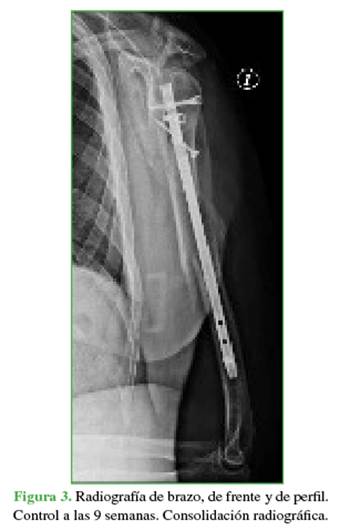

Durante el seguimiento, se comprobó la mejoría funcional progresiva y constante en la flexión activa del pulgar e índice. La fractura consolidó a las nueve semanas de la intervención (Figura 3).

Las radiografías de húmero, de frente y de perfil mostraron una fractura diafisaria del húmero izquierdo (OTA/ AO 12A1; Figura 2).